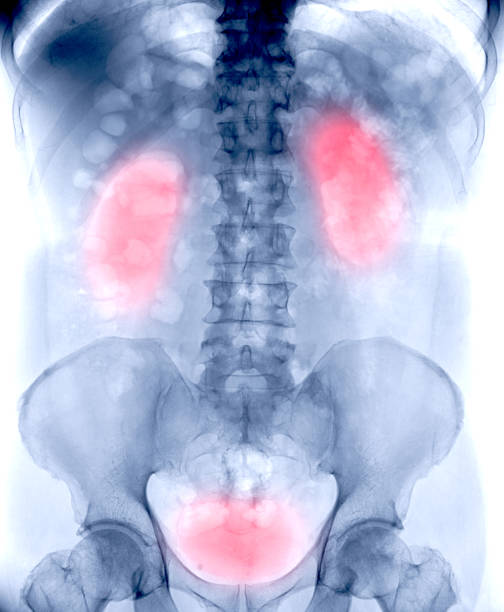

신우신염이란? 상부 요로계에 생긴 세균 감염

신우신염은 **신장과 신우(renal pelvis)**에

세균이 침투해 염증이 발생하는 감염 질환입니다.

대부분 하부 요로계, 즉 방광이나 요도에서 시작된 세균이

상행성으로 올라가 신장 부위까지 확산되며 생깁니다.